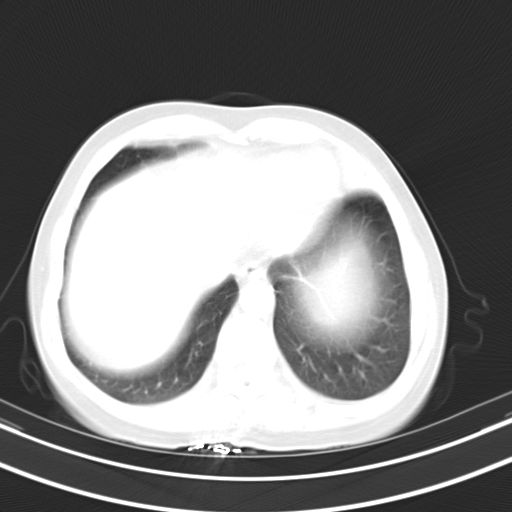

女,47岁,咳嗽胸痛一个星期,我们考虑肺结核,左下肺病灶肿瘤像不像,请高手指点。急。

右肺考虑炎症,建议抗炎后复查,左肺下叶考虑肺不张。

炎性灶;【1楔状实变影,有支气管气象,2近端纹理影增重】

右肺上叶前段积左肺舌叶炎症,建议严格抗炎后2周复查!

右肺上叶尖后段班片影不能出外肺结核。左肺舌叶三角形实变影,增强明显。考虑炎性病变

考虑两肺炎症,左胸腔积液,建议治疗后复查!

考虑炎性病变,左肺舌叶病灶需要与早期肺脓肿鉴别(结合实验室),左侧少量胸腔积液。

右肺为炎性改变,左肺病灶影像所见1、楔状实变影,边缘呈刀切样,见支气管气象,2、近端纹理影增重。

并从一元化来解释,还是符合炎性病灶。建议抗炎后复查。

两肺病变考虑炎症可能性大。(左肺病变呈楔状实变影,有支气管气象,近端纹理影增重)。

1)右肺上叶前段及左肺上叶舌段感染性病变;建议抗炎治疗后复查。2)左侧少量胸腔积液。

考虑右肺上叶前段及左肺舌叶炎症,建议抗炎治疗后复查除外结核。

左肺舌叶病灶呈扇形分布,其内可见支气管影,胸膜面光滑,不支持肿瘤病变。